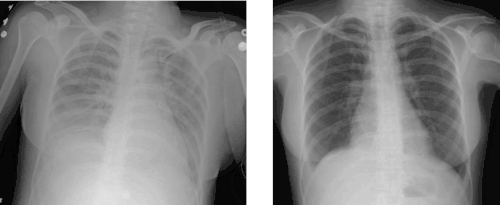

Transfusion-related acute lung injury (TRALI) is the serious complication of transfusion of blood products that is characterized by the rapid onset of excess fluid in the lungs.[1] It can cause dangerous drops in the supply of oxygen to body tissues. Although changes in transfusion practices have reduced the incidence of TRALI, it was the leading cause of transfusion-related deaths in the United States from fiscal year 2008 through fiscal year 2012.[2]

It is often impossible to distinguish TRALI from acute respiratory distress syndrome (ARDS). The typical presentation of TRALI is the sudden development of shortness of breath, severe hypoxemia (O2 saturation <90% in room air), low blood pressure, and fever that develop within 6 hours after transfusion and usually resolve with supportive care within 48 to 96 hours. Although low blood pressure is considered one of the important signs for diagnosing TRALI, in some cases high blood pressure can occur.[3]